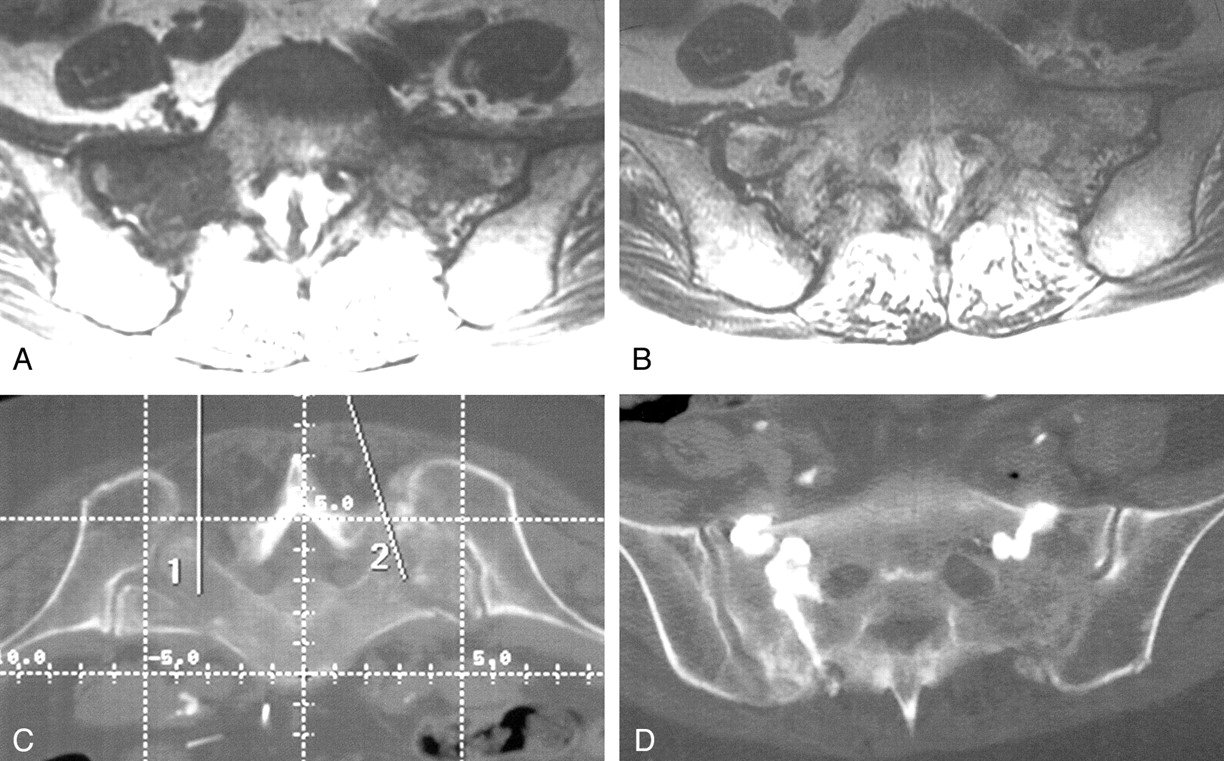

MR images obtained in a 74-year-old bedridden woman with severe lower back pain (Fig 3A and B) revealed edema within the sacrum, consistent with a sacral insufficiency fracture. Sacroplasty was performed in the CT suite, which greatly simplified needle placement (Fig 3C). Needle placement in the sacrum was performed by using CT guidance. A portable C-arm fluoroscope was brought to the CT suite and used to monitor cement injection. Postoperative CT confirmed the sacral cement placement (Fig 3D). The patient’s pain greatly diminished after the procedure, but she was lost to follow-up.

Case 3, a 74-year-old woman with sacral insufficiency fracture.

A and B, Preoperative sacral MR images show low-T1 (A[TR/TE, 450/14]) and high-T2 (B[4000/99]) signal intensity, consistent with the edema from a sacral insufficiency fracture.

C, Pelvic CT scan illustrates the two intended needle paths, simplifying needle placement during sacroplasty.

D, Postoperative CT confirms cement location.